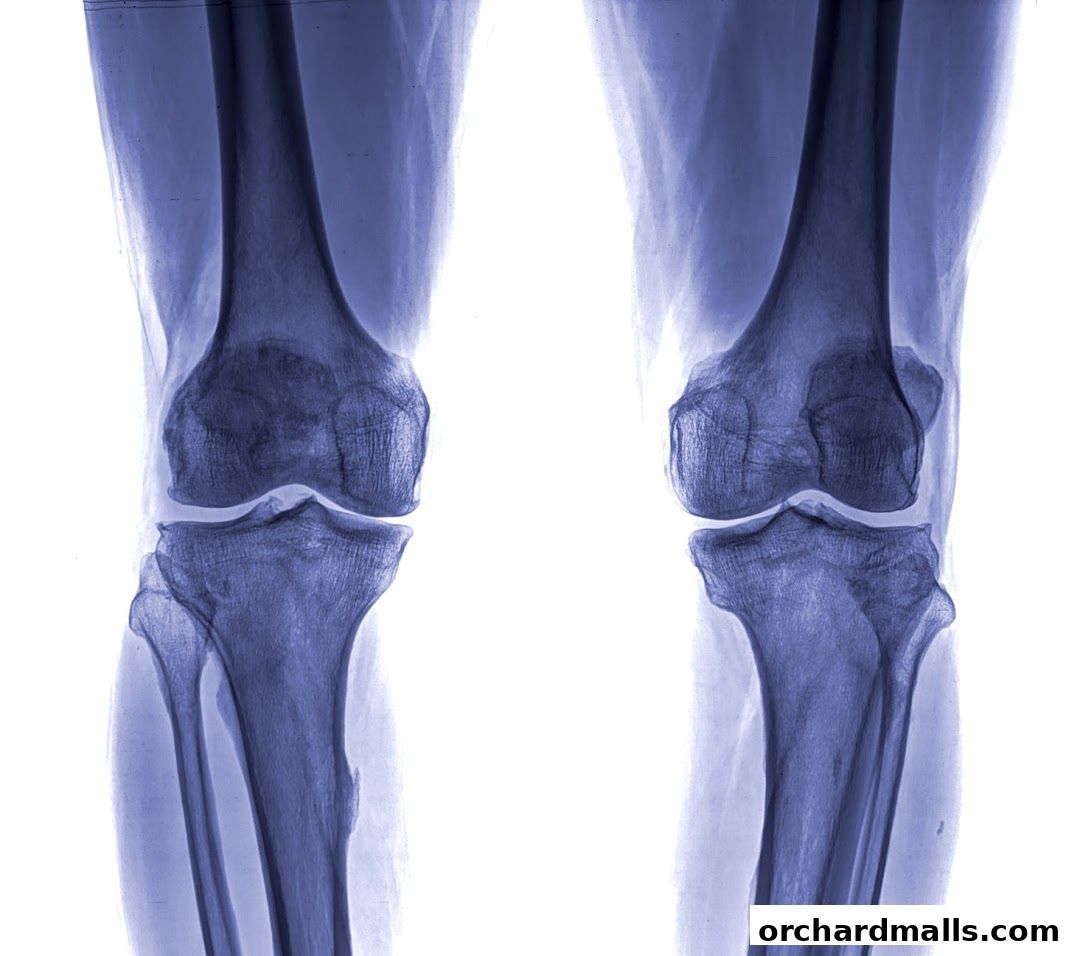

X-ray images of two human knees, showcasing bone structure and joints.